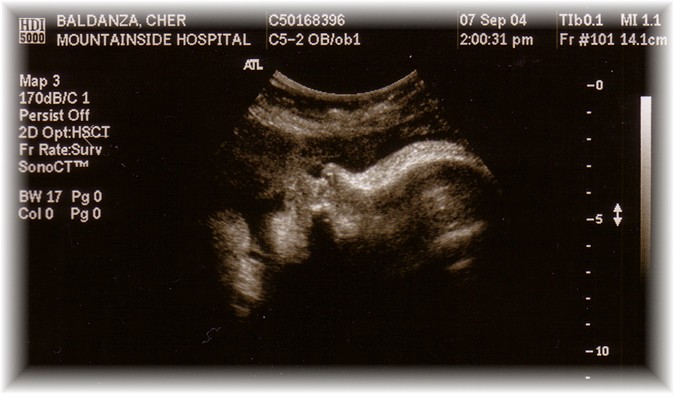

Jay Jay's In Utero Page

Jay Jay's In Utero Page!